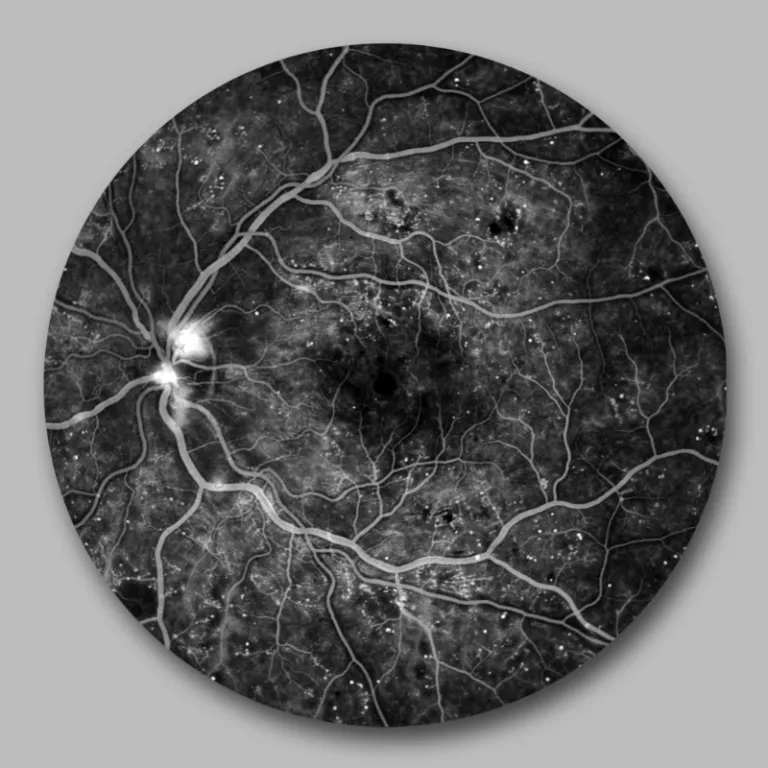

Angiographie der Netzhautgefäße mit Darstellung von neugebildeten Gefäßen am Sehnervenkopf

Zeigen sich Bildungen neuer instabiler Gefäße, so handelt es sich um eine proliferative Retinopathie. Diese Neubildungen führen zu Einblutungen sowohl in die Netzhaut als auch den Glaskörperraum, wodurch das Sehen – je nach Blutmenge – eingeschränkt wird.

Die Netzhaut wird aufgrund der diabetischen Gefäßveränderungen stellenweise schlecht mit Sauerstoff und Nährstoffen versorgt. Dadurch werden bestimmte Wachstumsfaktoren (VEGF) ausgeschüttet, die zur Bildung neuer Gefäße führen.